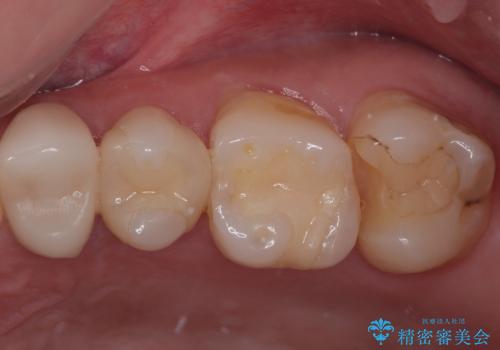

- プラスチックの詰め物が取れたとのことで来院された患者様です。神経の状態を検査し、正常な状態を確認してから残っている自分の歯の量を考慮しセラミックインレーにて修復しました。

拡大鏡視野下でコンポジットレジン、虫歯の除去を行い、セラミックインレーに適した形に整えました。